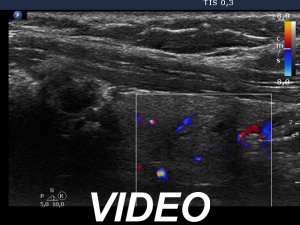

Ultrasonography. The thyroid was echonormal and presented several discrete lesions, most had no significance. The only possible relevant lesion was a minimally-moderately hypoechogenic nodule in the lower third of the left lobe.